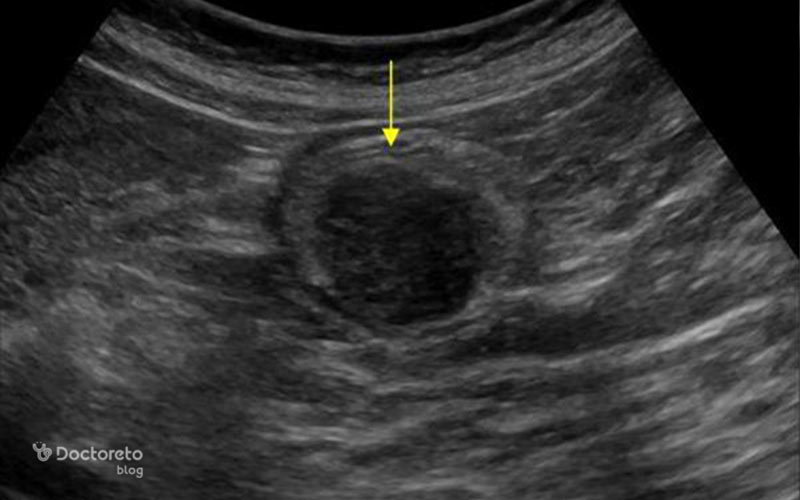

عکس تصویربرداری های سرطان معده خوش خیم

تصویربرداری پزشکی مانند سیتیاسکن و MRI به پزشکان کمک میکنند تا موقعیت، اندازه و ماهیت تومورهای معده را بررسی کنند. در ث تومورهای خوشخیم نیز این روشها کاربرد دارند تا احتمال نفوذ به بافتهای مجاور یا تبدیل احتمالی به بدخیم بیشتر و با دقت بالاتر ارزیابی شود. عکس این بخش نمونهای از این نوع تصویربرداریها را نشان میدهد.

عکس سی تی اسکن سرطان معده خوش خیم

سیتیاسکن ابزار قوی دیگری برای ارزیابی تومورهای معده است. این روش تصویربرداری به ویژه در تشخیص اندازه، موقعیت و ارتباط آنها با ساختارهای اطراف کاربرد دارد. حتی برای سلولهای خوشخیم سرطانی هم سیتیاسکن اطلاعات ارزشمندی در مورد چگونگی رشد و وضعیت بیمار ارائه میدهد. استفاده از این تصاویر کمک میکند تا پزشک نگاهی دقیقتر به تومور معده داشته باشد.